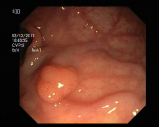

4.1.7 Gastrointestinal endoscopy

Endoscopies are used to detect diseases in the human digestive system. Images from inside the gastrointestinal tract can help physicians detect diseases early. The used dataset 777https://www.kaggle.com/datasets/abdallahwagih/kvasir-dataset-for-classification-and-segmentation contains eight image categories of the digestive system obtained through the endoscopy imaging technique, as shown in Fig. 8. There are a total of images that can be used in training and testing ML algorithms.